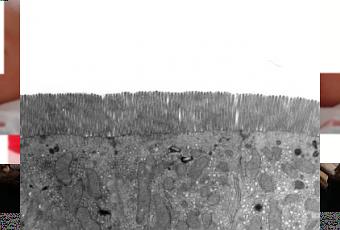

(Visuel » épithélium de l’intestin « @ Institute of Food Research and Univerisity of Siena)